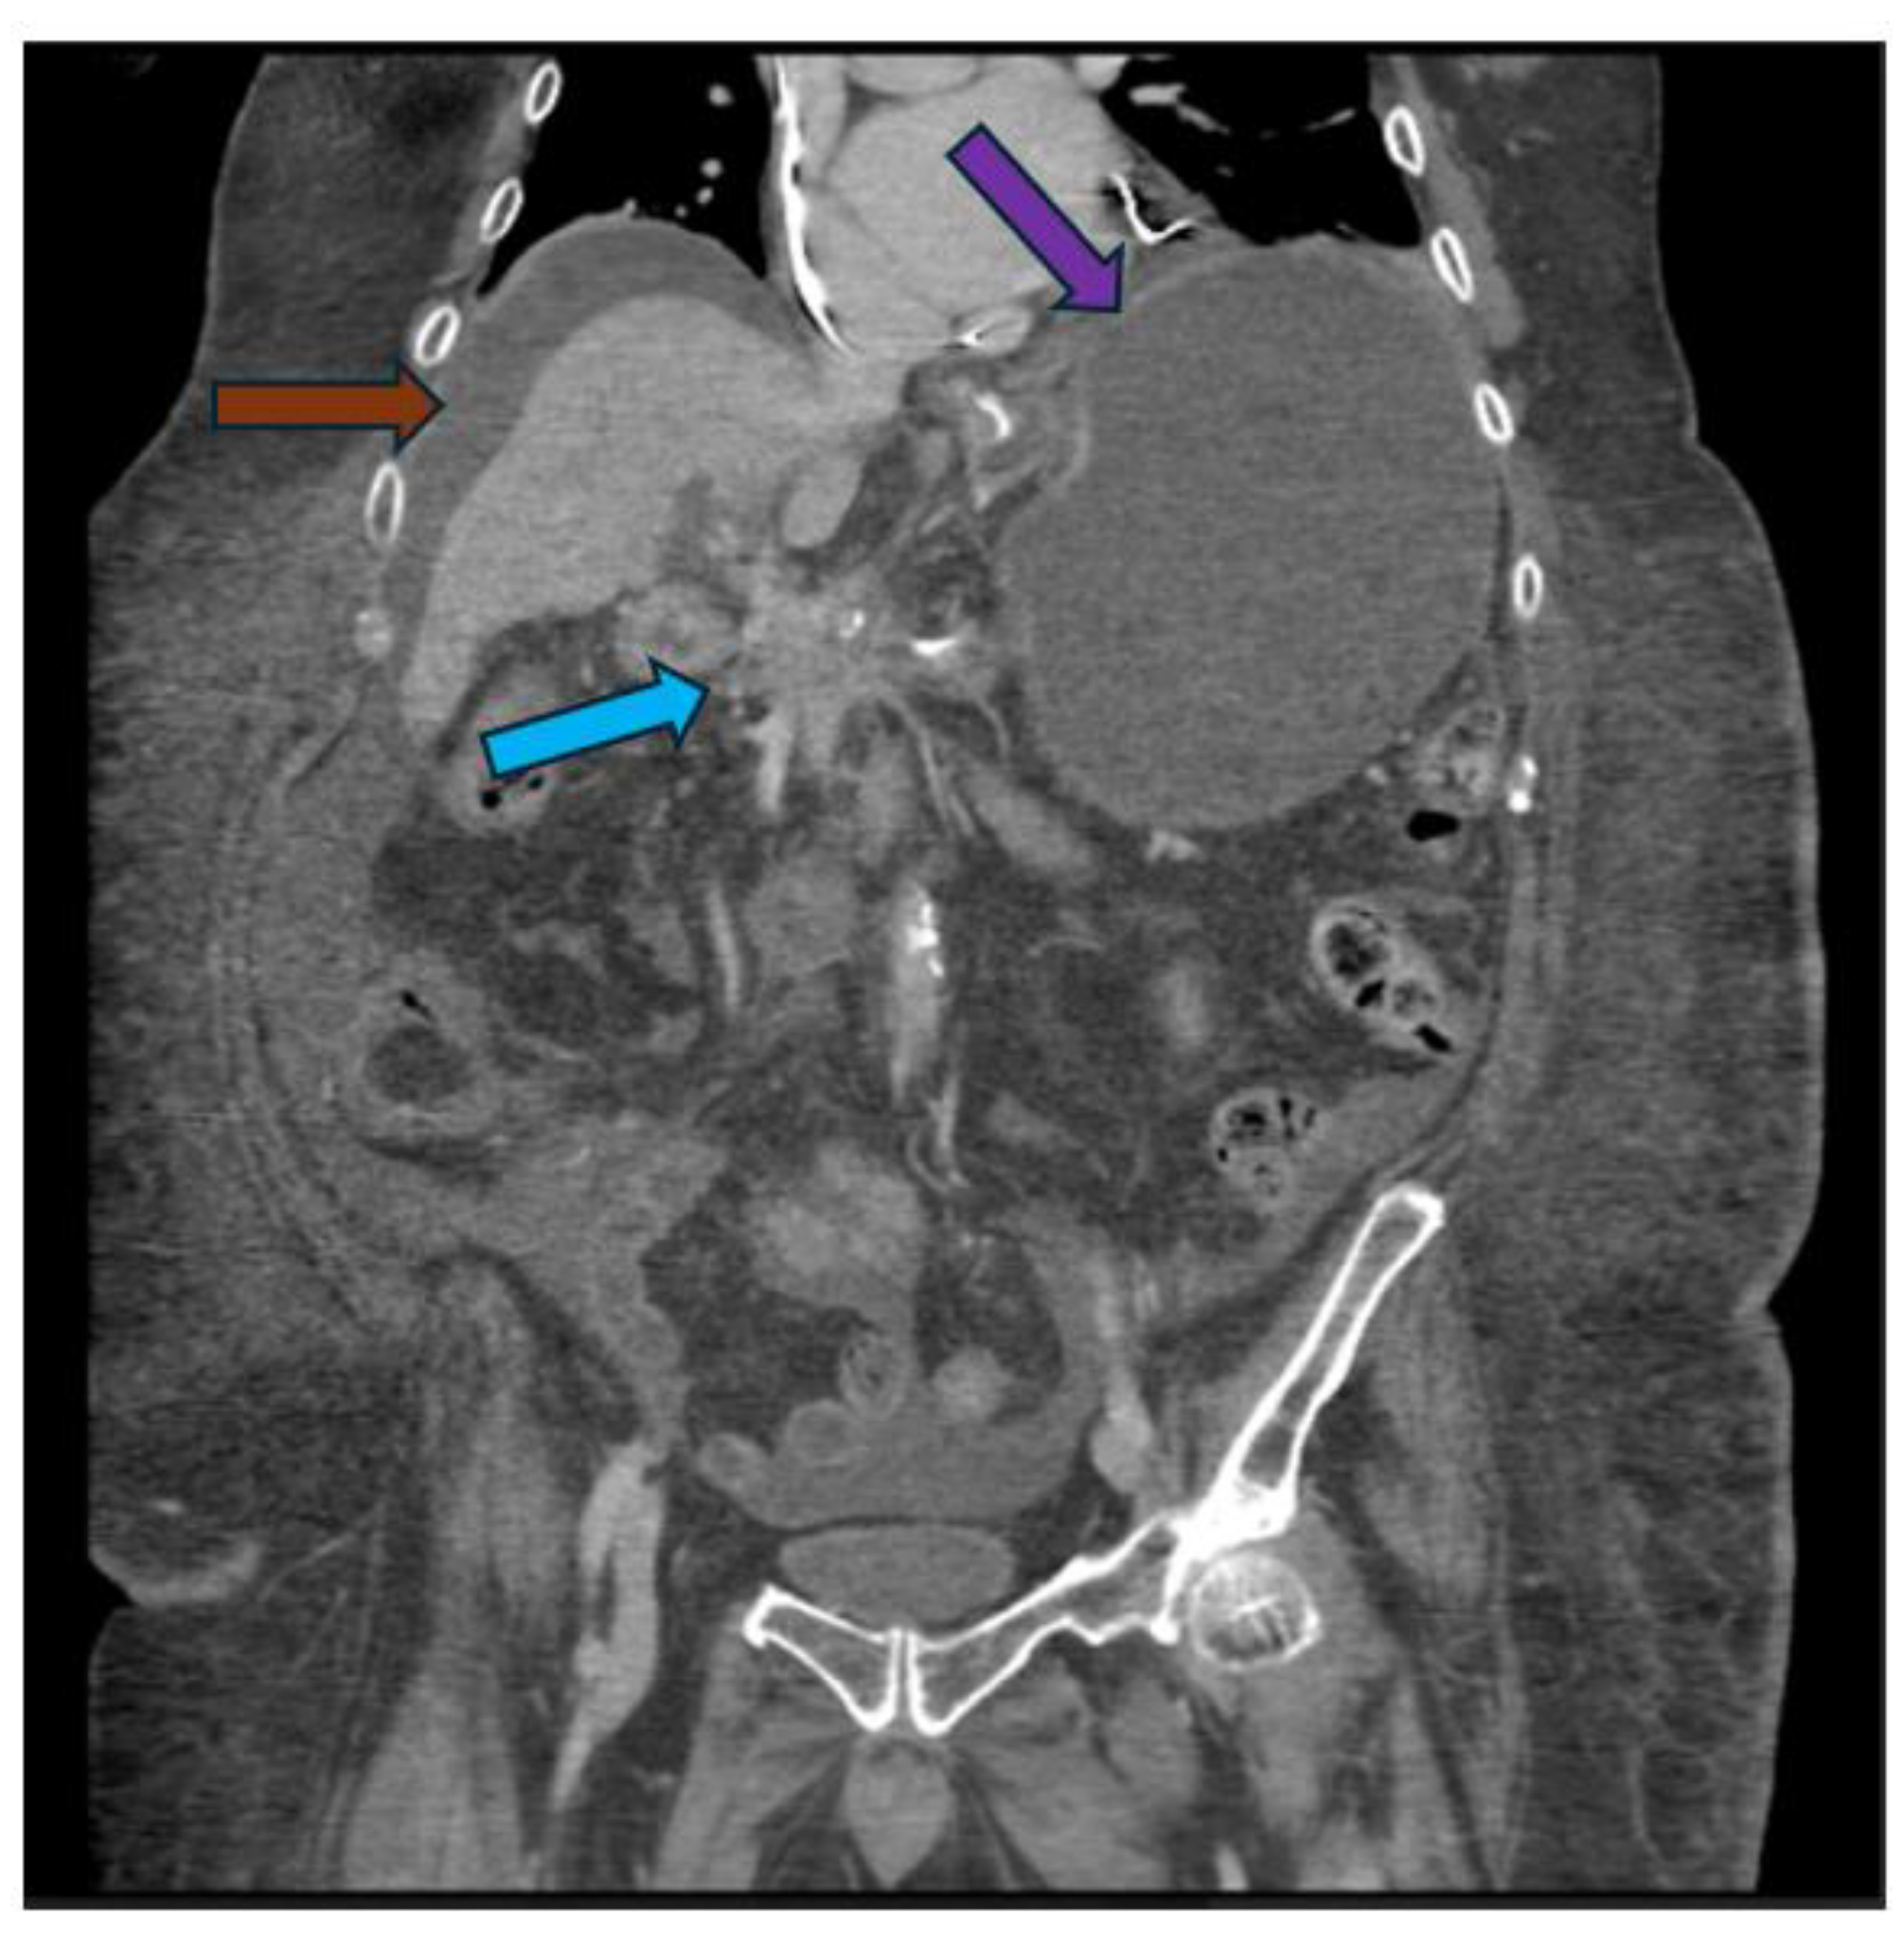

Pancreatic cancer is an aggressive malignancy, and the current 5-year survival rate in the United States, according to the Surveillance, Epidemiology, and End Results Program data, approximates 12%. Although the current standard for resectable pancreatic cancer most commonly includes neoadjuvant chemotherapy prior to a curative resection, surgery in the majority of patients has historically been palliative. The latter interventions include open or laparoscopic bypass of the bile duct or stomach in cases of obstructive jaundice or gastric outlet obstruction, respectively. Non-surgical interventional therapies started with percutaneous transhepatic biliary drainage (PTBD), both as a palliative maneuver in unresectable patients with obstructive jaundice and to improve liver functions in patients in whom surgery was delayed. Likewise, interventional radiologic techniques included placement of plastic and ultimately self-expandable metal stents (SEMS) through PTBD tracts in patients unresectable for cure as well as percutaneous cholecystostomy in patients who developed cholecystitis in the context of malignant obstructive jaundice. Endoscopic retrograde cholangiopancreatography (ERCP) and stent placement (plastic/SEMS) was subsequently used both preoperatively and palliatively, and this was followed by, or undertaken in conjunction with, endoscopic gastro-duodenal SEMS placement for gastric outlet obstruction. Although endoscopic ultrasound (EUS) was initially used to cytologically diagnose and stage pancreatic cancer, early palliation included celiac block or ablation for intractable pain. However, it took the development of lumen-apposing metal stents (LAMS) to facilitate a myriad of palliative procedures: Cholecystoduodenal, choledochoduodenal, gastrohepatic and gastroenteric anastomoses for cholecystitis, obstructive jaundice, and gastric outlet obstruction, respectively. In this review, we synopse these procedures which have variably supplanted surgery for the palliation of pancreatic cancer in this rapidly evolving field.